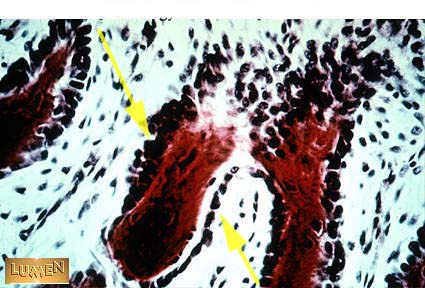

What are these cells?

Answer

Osteoblasts